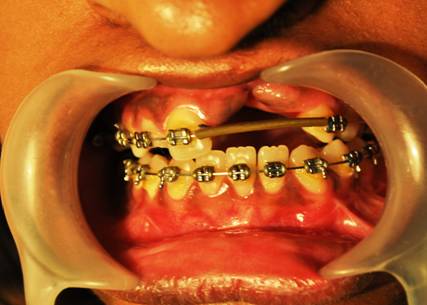

MAXILLARY LEFORT I ADVANCEMENT

BILATERAL SAGITAL SPLIT OSTEOTOMY SETBACK |